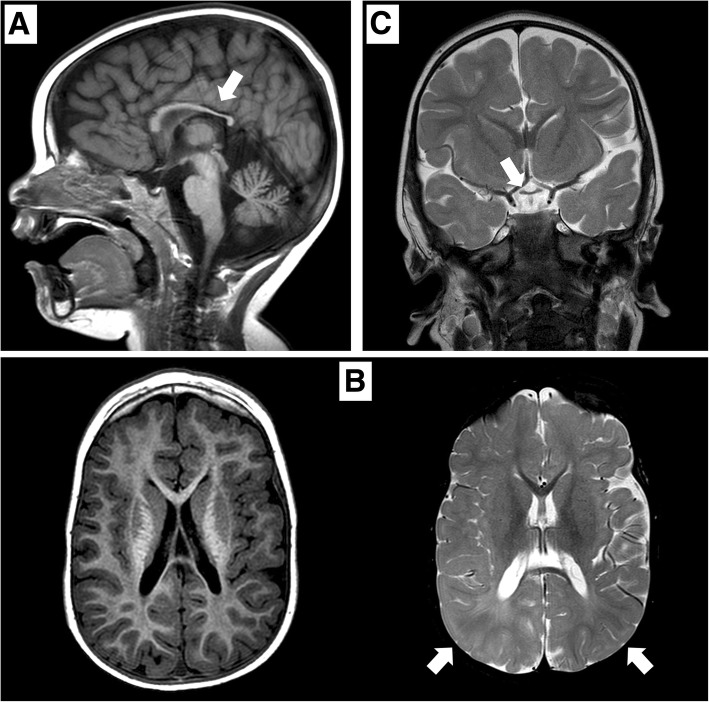

矢狀位 T1 加權(quán)圖像顯示胼胝體發(fā)育不全(白色箭頭)。 b 軸向 T1 加權(quán)(左)和軸向 T2 加權(quán)(右)圖像顯示胼胝體發(fā)育不全和雙側(cè)皮層下頂葉白質(zhì)(白色箭頭)中改變的、不明確的信號。 c 顯示視交叉發(fā)育不全的冠狀 T2 加權(quán)圖像(白色箭頭)

在 2 歲時,患者無法保持目光接觸,也沒有發(fā)展語言技能。 直到 3 歲時,他才能獨立坐下。此時,頭顱 MRI 顯示雙側(cè)視神經(jīng)發(fā)育不全,并證實胼胝體發(fā)育不全(圖 (圖 1).1)。 為評估先天性心臟缺陷而進行的超聲心動圖顯示無阻塞的室間隔肥大。